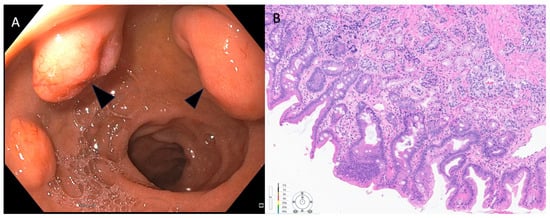

2.2. Stomach

| Stomach | Surveillance could be an option for Type-1 g-NENs < 1 cm. Treatment choice should be based on assessment of patient’s coexisting health conditions and local expertise. Observation is not favoured for Type-2 and Type-3 n-NENs. Local or limited excision can be considered, but must be tailored to the patient based on multidisciplinary evaluation at centers with expertise. | EGD ± NBI with biopsy, E-EUS EUS-FNA, FNB SINKMIAB | ESD | EMR EFTR Underwater EMR | Endoscopic resection recommended only for lesions < 2 cm with no suspicion for lymphovascular invasion |

| Stomach | Type 1 <1 cm Surveillance or ER 1–2 cm Endoscopic surveillance every 3 years vs. ER >2 cm SR. ER can be considered if feasible on a case-by-case manner EUS recommended for NEN > 1 cm to assess depth of invasion Type 2 <1 cm Surveillance or ER 1–2 cm ER or SR >2 cm SR EUS recommended for NEN > 1 cm to assess depth of invasion Type 3 Surgical resection | EUS is recommended in tumors >1 cm Endoscopic resection in type 1 NEN larger than 1 cm. ESD and FTR are more effective to achieve R0 resection compared to EMR. Endoscopic resection may be considered for localized type III G1 gNETs ≤ 10 mm, and occasionally larger tumors with Ki-67 < 10% and <15 mm in diameter if the risks of surgical resection are high. |